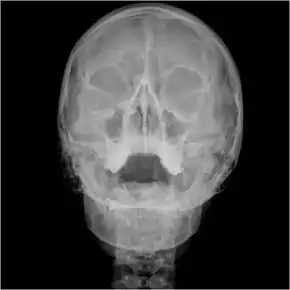

Orbital x-ray

Waters view showing diffuse prominent mucosal thickening in the right maxillary sinus and mild nmucosal thickening in the left maxillary sinus.

Orbital x-ray or orbital radiography is an x-ray of both left and right eye sockets, to include the Frontal Sinuses and Maxillary Sinuses.

An orbital x-ray usually requires only one view unless the requester is looking for evidence of metallic fragments, in which case two projections can be made. One with the eyes looking up, one with the eyes looking down. These views will show any movement of fragments and helps rule out false positives / artefacts which may be present on the image receiver. Two other important views are the Water's view which helps visualise the anterior orbital floor and maxillary sinuses; and the Caldwell view which helps to visualise the frontal and ethmoid sinuses and posterior orbital floor.[3]